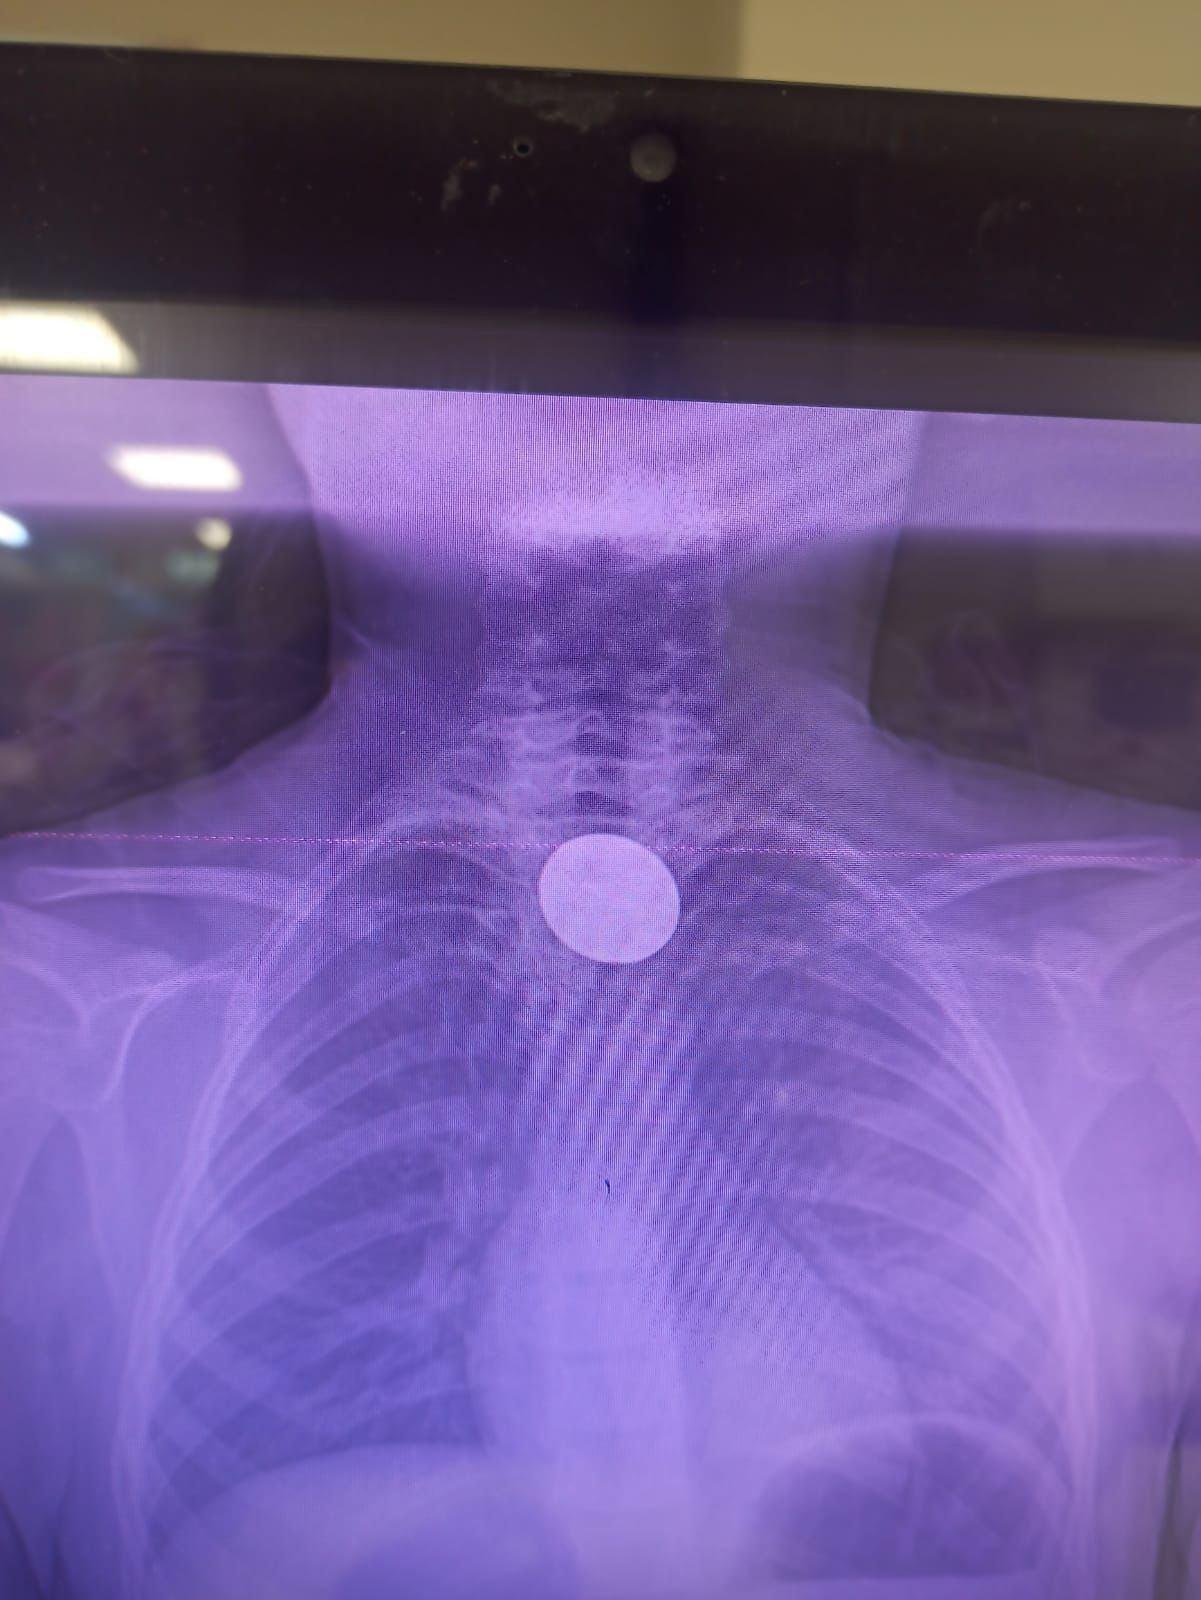

Siirt'te 8 yaşındaki çocuğun boğazına madeni 5 lira kaçtı. Hastaneye götürülen çocuğu doktorların titiz çalışması kurtardı.

Paylaşılan bilgilere göre 8 yaşındaki Y.K., yabancı cisim yutma şikayetiyle ailesi tarafından Siirt Eğitim ve Araştırma Hastanesine götürüldü.

Y.K.'nın yemek borusuna kadar ilerlediği tespit edilen madeni para, gastroenteroloji uzmanı Dr. Yaren Dirik ve kulak burun boğaz hekimi Yasin Gökçınar tarafından müdahale edilerek çıkartıldı.

"Hastanemize başvuran 8 yaşındaki hastamızın yemek borusuna kaçan madeni para, gastroenteroloji ve KBB ekiplerimizin koordineli ve titiz çalışmasıyla herhangi bir komplikasyona yol açmadan başarılı bir şekilde çıkarılmıştır. Operasyon süreci sorunsuz geçmiş olup hastamızın genel durumu iyidir."